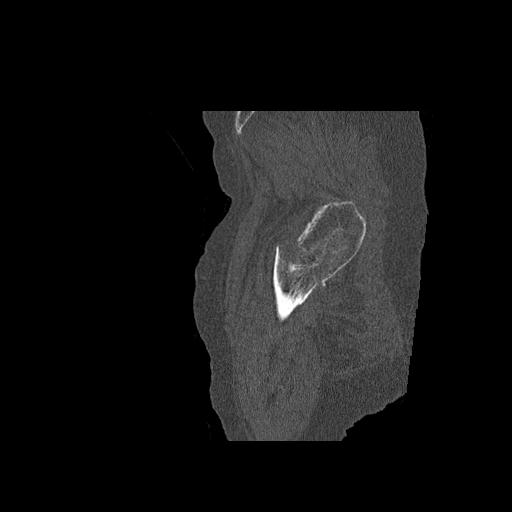

49554 3/13 膝 4R 3/16 4R 1/18 2R 78歳男性 膝蓋骨骨折